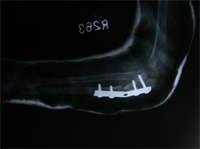

Rush Rodding Periosteal Grafting

Newer Fassier - Duval rod in an older child. About CPTCPT is a disorder of the tibia where there is a propensity for recurrent fractures, poor healing of bone and need for multiple operations. Current methods of treatment of CPT have evolved to give much more consistent results than previously possible. Special methods are available to achieve union. |